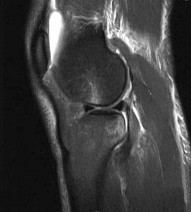

Question 16:

A 19-year-old football player undergoes primary anterior cruciate ligament (ACL) reconstruction using a bone-patellar tendon-bone (BPTB) autograft. In comparing the biomechanical properties of the graft to the native ACL, which of the following statements is true regarding stiffness?

Correct Answer: The BPTB graft is approximately 3 to 4 times stiffer than the native ACL

The native ACL has a stiffness of approximately 242 N/mm. A 10-mm BPTB graft has a stiffness of approximately 620 N/mm (some studies cite up to 3x, or ~730 N/mm depending on exact width and testing parameters), making it significantly stiffer than the native ACL. A quadrupled hamstring graft is even stiffer, typically around 800 N/mm.